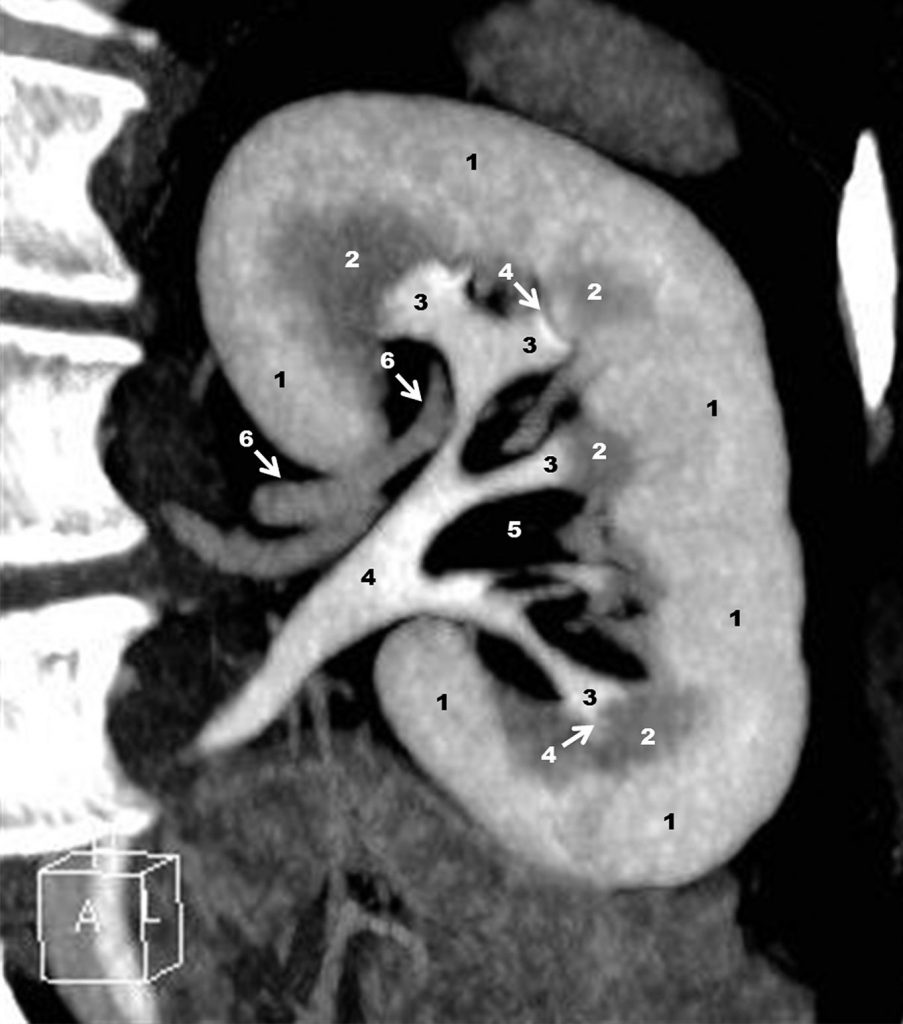

Fig. 19.7. Uroscanner : reconstruction en mode MPR (Multiplanar Reconstruction) centrée sur le rein gauche, 7 minutes après une première injection intraveineuse de produit de contraste iodé et 70 secondes après injection d’un deuxième bolus de produit de contraste.

1. Cortex rénal. 2. Médullaire rénale (pyramide de Malpighi). 3. Petits calices. 2, 3. Complexe papillocaliciel. 4. Fornix. 5. Tissu adipeux du sinus du rein. 6. Branches de l’artère rénale au hile et dans le sinus.

Source : CERF, CNEBMN, 2022.